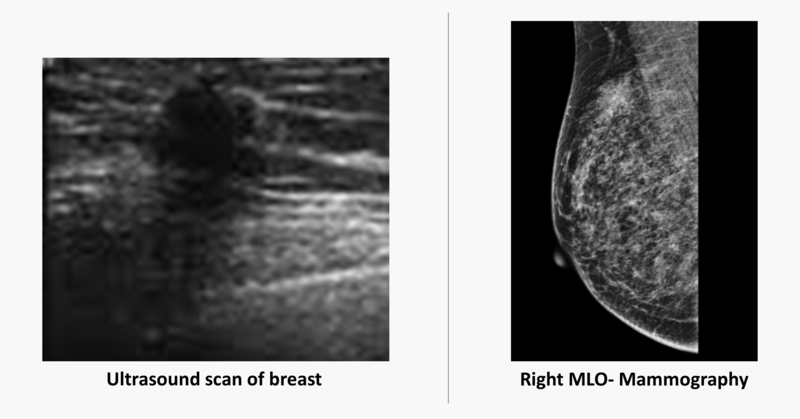

- Digital mammogram demonstrates a spiculated density with architectural distortion in the upper outer quadrant of the right breast (straight long arrow)

- A high resolution ultrasound scan demonstrates a spiculated hypoechoic mass (curved arrow) with distal acoustic shadowing (short straight arrow)